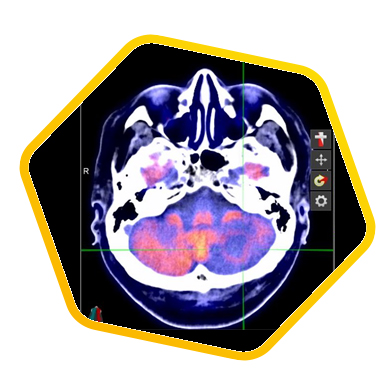

PET/CT scans with special tracers can show 3-dimensional images of blood flow and biomolecules deposition in the brain for diagnosis and monitoring the therapy progress of various neurological diseases, such as Alzheimer's, Dementia, Parkinson's disease, Huntingdon's chorea and autism. In 2018, the National Institute on Aging-Alzheimer's Association (NIA-AA) had revised the definition of Alzheimer's Disease (AD) from a syndrome diagnosed by a set of clinical criteria to a biological construct using abnormal protein deposits to define AD as a unique neurodegenerative disease that can lead to dementia. Our hospital has almost 20 years of experience in producing specific tracer to detect abnormal protein deposition in the brain.

- Epilepsy

For some types of epilepsy patients, PET/CT scans can localize the epilepsy-causing focus in the brain. Modern stereotaxic neurosurgery can then cure epilepsy permanently by excising the focus.